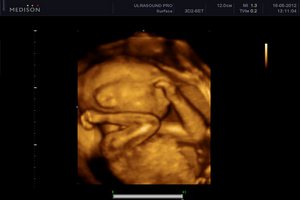

Вага дитини, до цього часу, становить близько 900 грам, його довжина 32 см від п'ят до маківки. Тепер вона дуже активна, і ви постійно це відчуваєте. Ворушіння плода нерідко бувають болючими для мами, малюк вже досить сильний і великий, стусани в печінку і сечовий міхур викликають неприємні відчуття. Але що поробиш, знаходьте в цьому радість, ваша дитина росте, і скоро ви зустрінетеся. Плід на 26 тижні, частіше за все, лежить головою вниз, але все ще може легко змінити положення, перевернувшись вниз попкою, і поки його передлежання ні про що не говорить і не повинно викликати у вас тривоги. Вага плоду набирається, переважно, за рахунок відкладення жиру і розвитку м'язів, в довжину він росте тепер трохи повільніше. Поки його шкіра все ще тонка і червона, однак зовсім скоро вона стане світлішою. Жир тепер відкладається не тільки коричневий, але і звичайний, на ручках і ніжках, округлюються щічки. Малюк змушений вже стійко утримувати ту позу, яка займає мінімум місця - притискаючи голову до грудей і згорнувшись клубочком. Він живе тепер в світі звуків, смаків, і він здатний бачити.

Ви на цьому тижні можете відвідати гінеколога, а можете і зовсім не здавати ніяких аналізів, все залежить від призначень лікаря. УЗД на 26 тижні вагітності буває рідко і лише строго за показаннями.